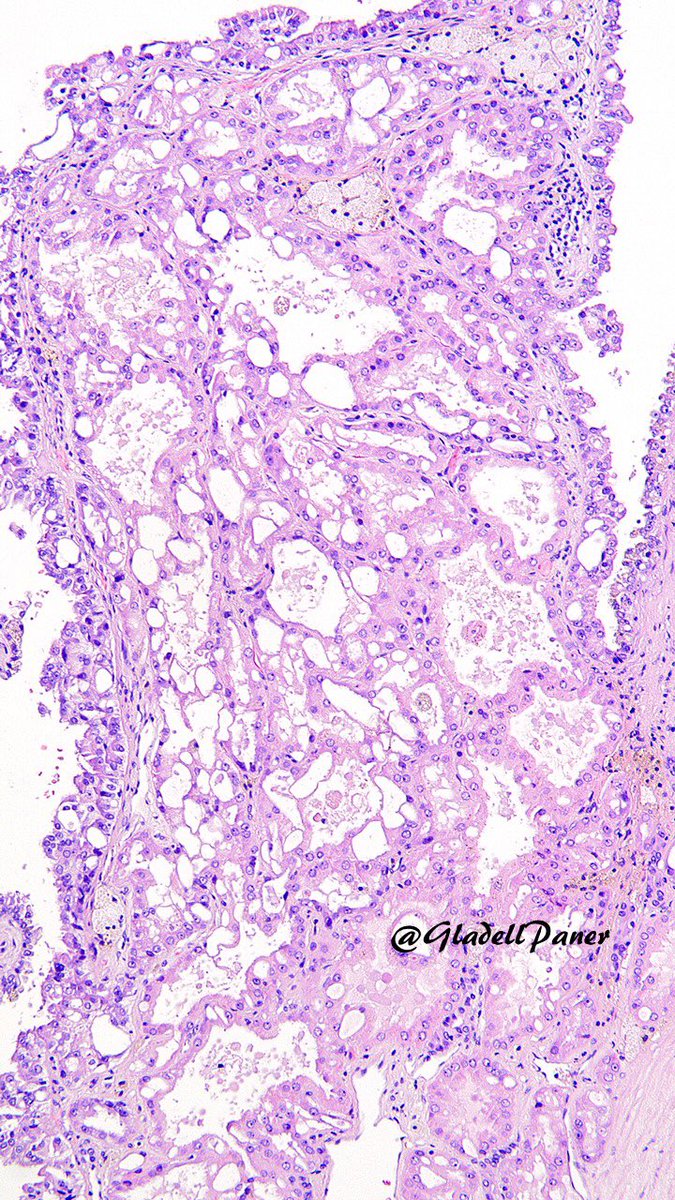

Clinical history often gives away the diagnosis of this uncommon #renal tumor. But letโ€™s diagnose this through morphology side with its unique pattern as clue. ๐Ÿ” #OnePicDx What is your diagnosis on this #nephrectomy #GUPath tweeps? Answer in comment๐Ÿ‘‡๐Ÿ‘‡๐Ÿ‘‡

Clinical history often gives away the diagnosis of this uncommon #renal tumor. But letโ€™s diagnose this through morphology side with its unique pattern as clue. ๐Ÿ” #OnePicDx

What is your diagnosis on this #nephrectomy #GUPath tweeps?

Answer in comment๐Ÿ‘‡๐Ÿ‘‡๐Ÿ‘‡